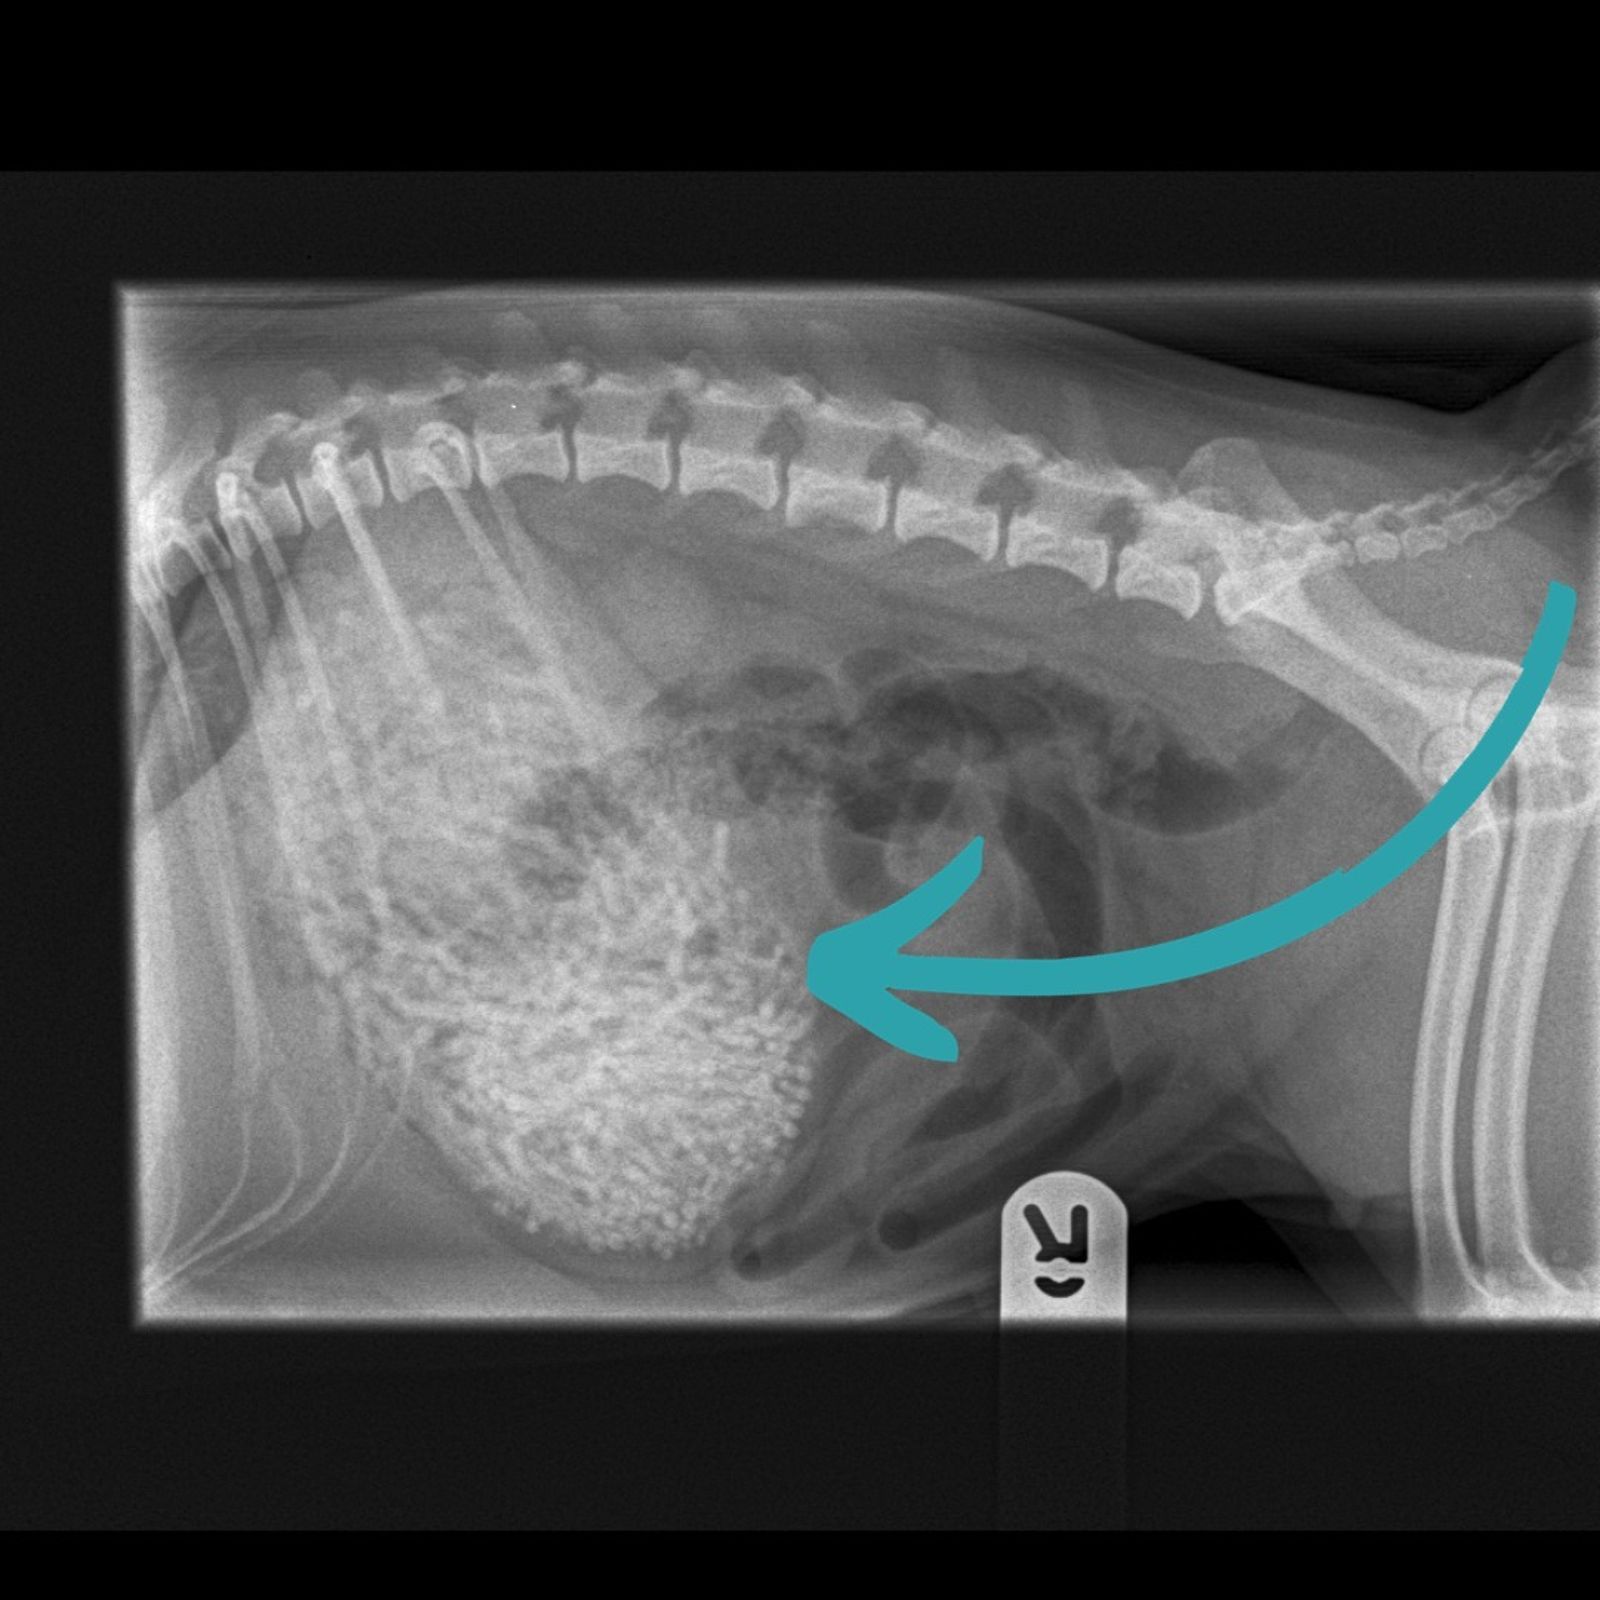

▲獸醫從X光發現哈姆腹部裡有奇怪東西。(翻攝自臉書Newton Clarke Veterinary Surgeons)

獸醫從X光發現哈姆腹部裡有奇怪東西,手術取出了50多條髮帶,重量約200公克,讓飼主相當震驚。